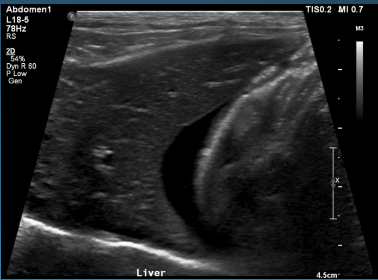

What is shown in this image?

biliary distention: -wall starting to thicken -sludge present that is starting to mineralize